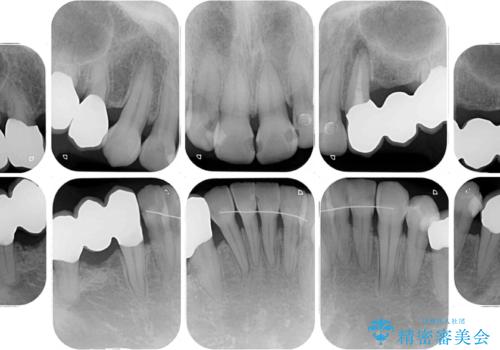

- 歯並びやグラグラする奥歯など、気になる所を全部治したいとのことで来院された患者様です。

奥歯は咬み合わせや歯周病により歯槽骨が失われていたり、むし歯や破折している歯などがあったりと、歯周病治療やインプラント補綴、矯正治療など、総合的に治療が必要と診断されました。

まずは歯周病治療やインプラント埋入を行い、環境が整った後にワイヤーを併用したインビザライン矯正を行い、オールセラミッククラウンにて補綴治療を行うこととしました。